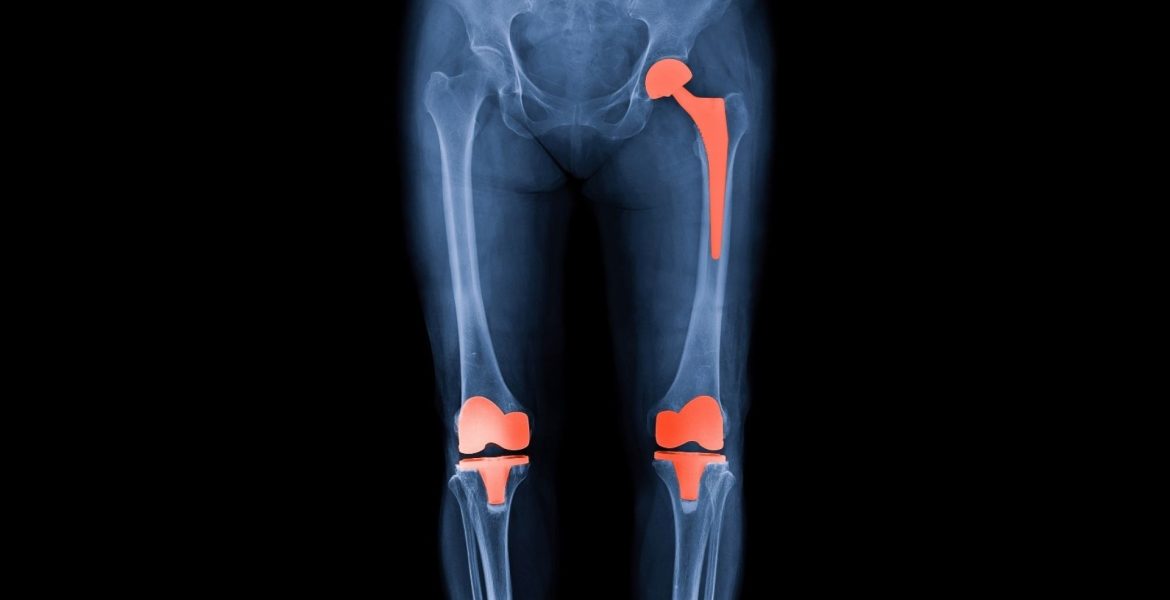

Diz ve Kalça Protezi Nedir?

Diz ve kalça protezi, ileri derecede eklem kireçlenmesi (artroz), travma sonrası hasarlar veya romatizmal hastalıklar nedeniyle işlevini kaybetmiş eklemlerin yapay protezlerle değiştirilmesi işlemidir. Bu cerrahi yöntem, hastaların günlük yaşam aktivitelerini ağrısız ve daha rahat şekilde yapabilmesini sağlar.